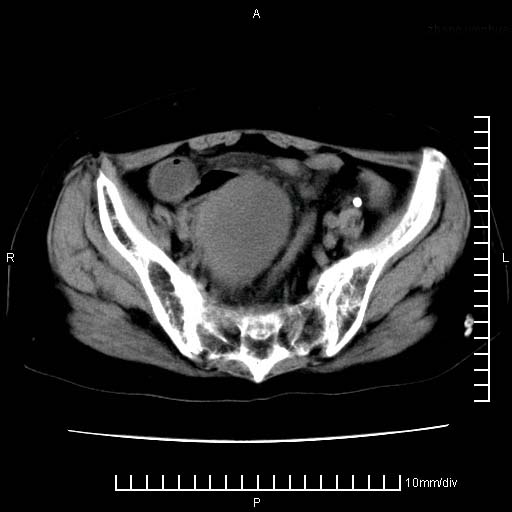

标题: CT24821:女性,70岁

下腹疼痛2月,加重并呕吐2天,下腹压痛,反跳痛。白细胞1万2.

下腹至盆腔较大包块,与邻近肠管关系密切,下腹疼痛2月,加重并呕吐2天,下腹压痛,反跳痛。白细胞1万2.

由于没有做肠道准备很难分清是哪根肠管,但看位置考虑为升结肠回盲部的问题,我首先考虑化脓性阑尾炎,不除外结肠癌合并感染化脓。建议做增强进一步明确。

盆腔脓肿伴盆腔积液

不知道大家可要注意下腹腔小肠旁不规则结节状灶,部分钙化,是否要考虑小肠腺癌.盆腔包块可能考虑脓肿.

考虑卵巢恶性肿瘤;盆腔积液。